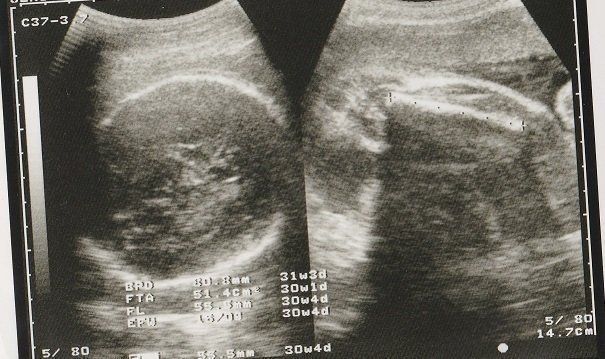

チャーミー小結さんの妊娠30週目のエコー写真

口をキュッとつぐむ様子も愛おしい表情。この頃は便秘がひどく、「酸化マグネシウム」を医師に処方してもらいました。この頃は安静にしながらも、週に1回催される母親学級へ車椅子で通い勉強していました。